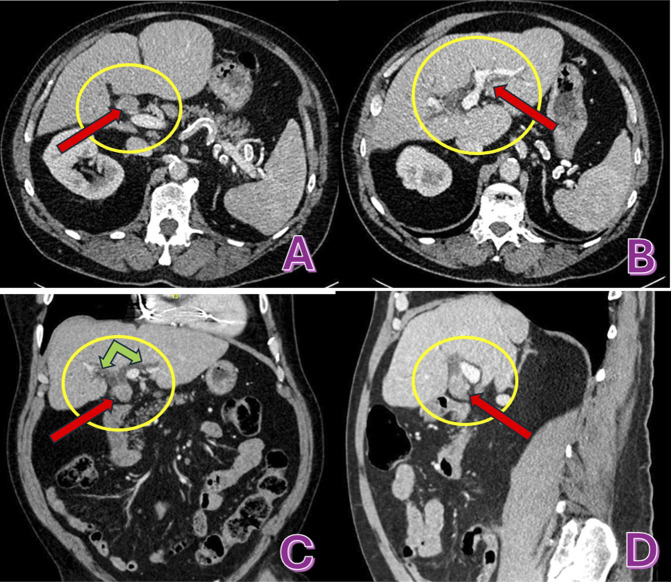

胆管癌是一种罕见的胃肠道恶性肿瘤,年发病率为每10万人0.3 - 6例,通常约95%的病例报告为腺癌。它可以是遗传易感性和各种危险因素共同作用的结果,如但不限于胆总管囊肿、胆石症/胆总管结石,但由于难以获得诊断组织,其诊断具有挑战性。在这项研究中,我们提出了一个具有挑战性的诊断病例,揭示了胆管门周区域未分化的破骨细胞样巨细胞癌。

Cholangiocarcinoma is a rare gastrointestinal malignancy with an annual incidence of 0.3 to 6 cases per 100,000, and, usually, it is reported as adenocarcinoma in about 95% of the cases. It can develop as a result of combination of genetic predispositions and various risk factors like but not limited to choledochal cysts, cholelithiasis/choledocholithiasis, yet its diagnosis is challenging due to difficulties in obtaining tissue for diagnosis. In this study, we present a challenging case in diagnosis that reveals undifferentiated carcinoma with osteoclast-like giant cells in the perihilar region of the bile duct.